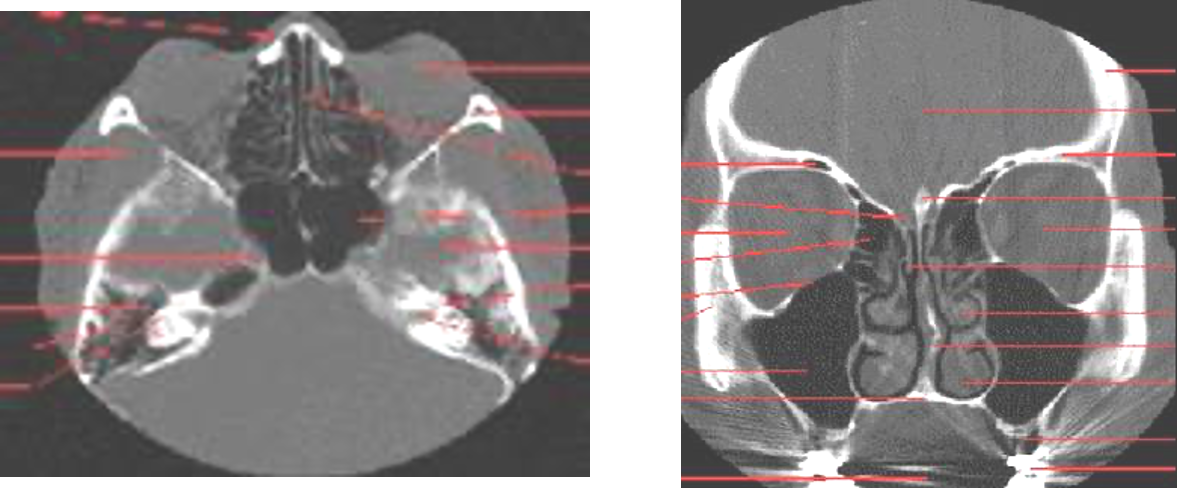

CT Paranasal Sinuses

- Axial

- Coronal